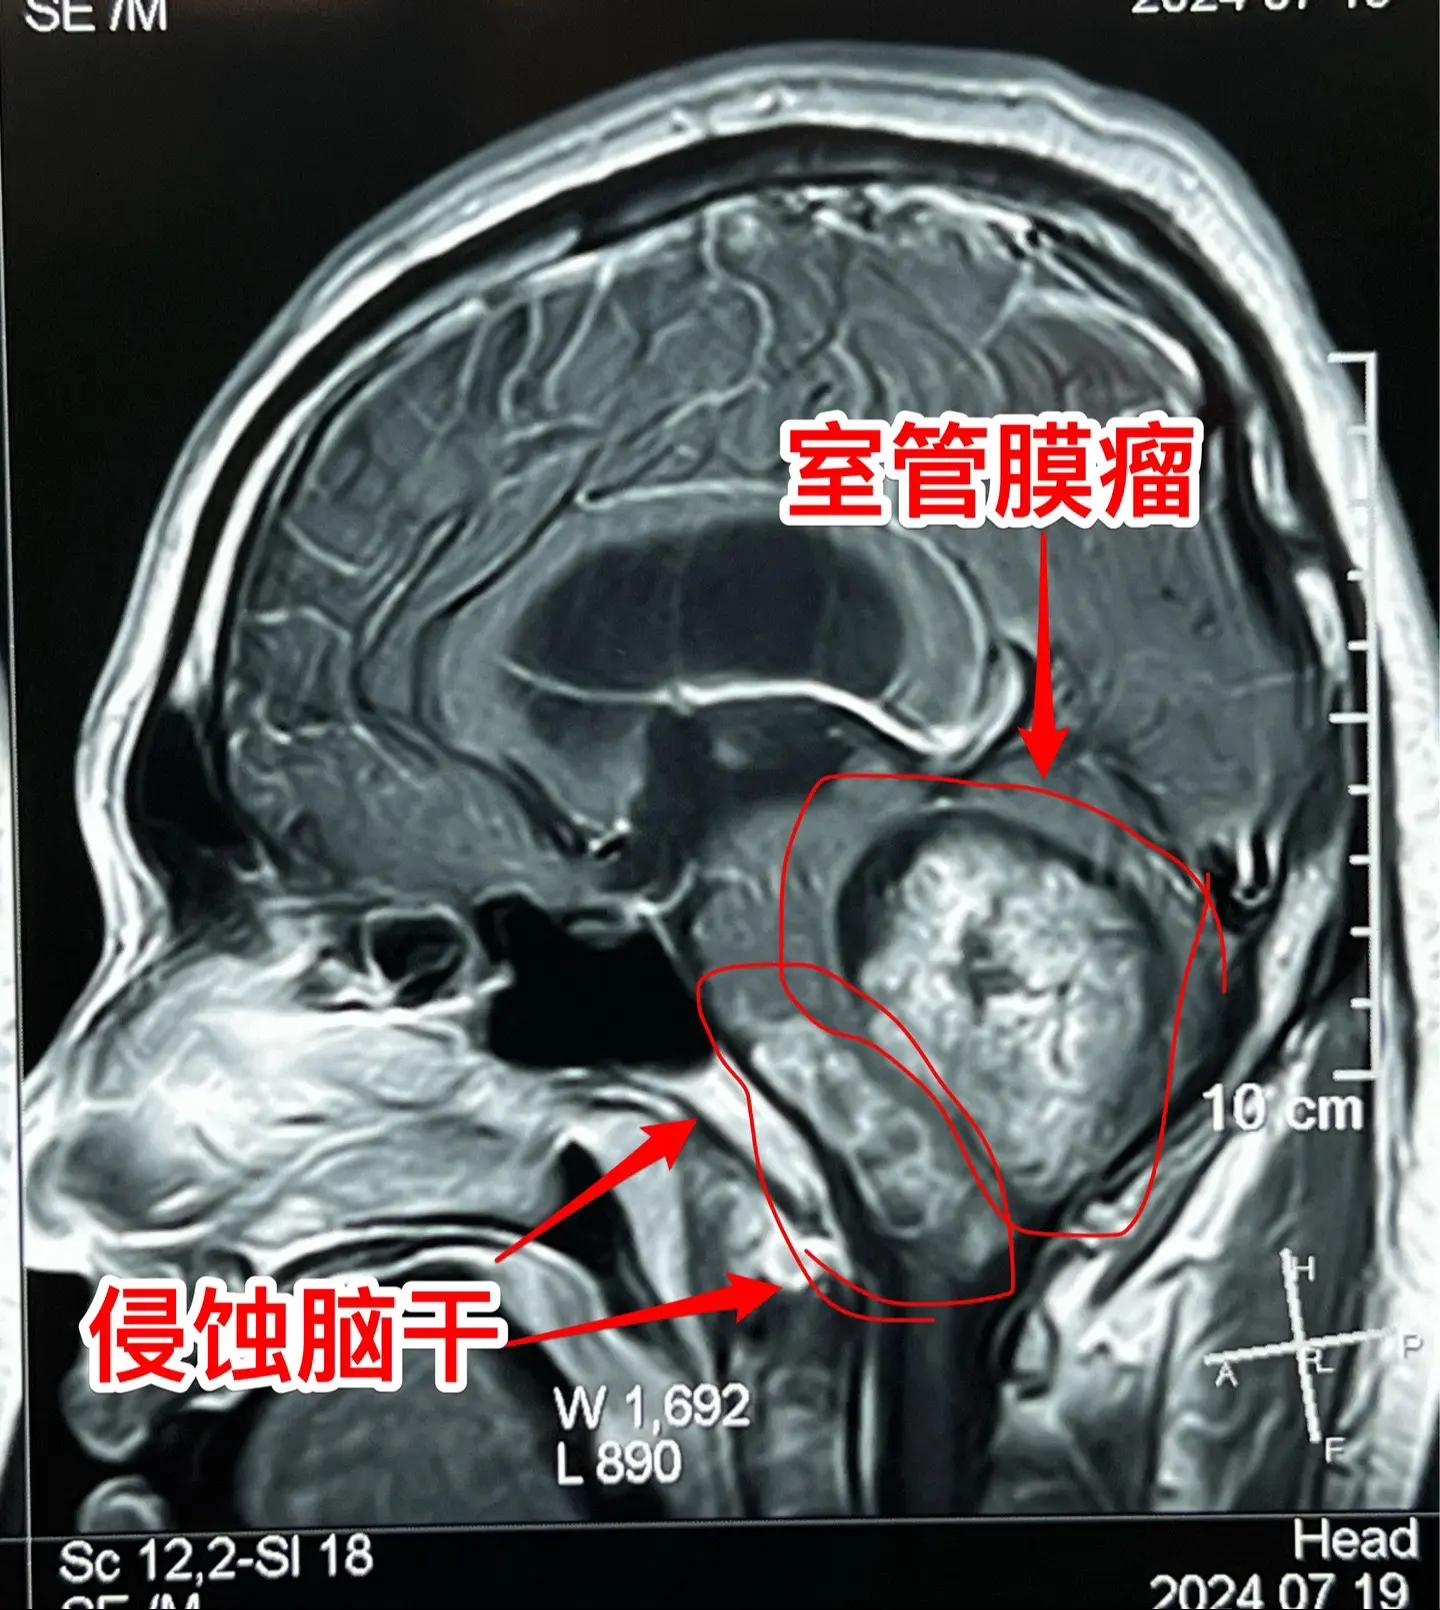

室管膜瘤是良性肿瘤还是恶性肿瘤?41岁的青海省病人,在八年前作过一次开颅手术,现在肿瘤复发了,而且体积很大,脑干实质也受到肿瘤侵蚀,病人有面瘫症状。

室管膜瘤是个奇怪的肿瘤,在不同的部位表现出来的生物学特性是不一样的。

室管膜瘤最常见的部位是在小脑,小孩子和大人均可见,即使是完全切除了,想获得治愈是很有难度的,一般认为是恶性肿瘤,化疗、放疗的效果也不确切。